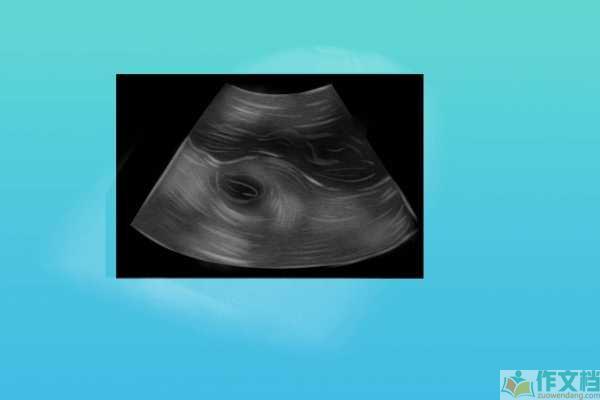

产检HS是什么意思产检HS是指胎儿侧脑室增宽的现象,这可能与染色体异常有关。在产检中,如果发现HS指标异常,需要进一步进行遗传学检查和评估,确定胎儿的健康状况。

胎儿侧脑室增宽(HS)的可能原因胎儿侧脑室增宽的原因有很多,最常见的是染色体异常,如唐氏综合征等。此外,孕妇在孕期感染某些病毒,如单纯疱疹病毒等,也可能导致胎儿侧脑室增宽。胎儿的神经系统发育异常或颅内出血等,也可能表现为侧脑室增宽。